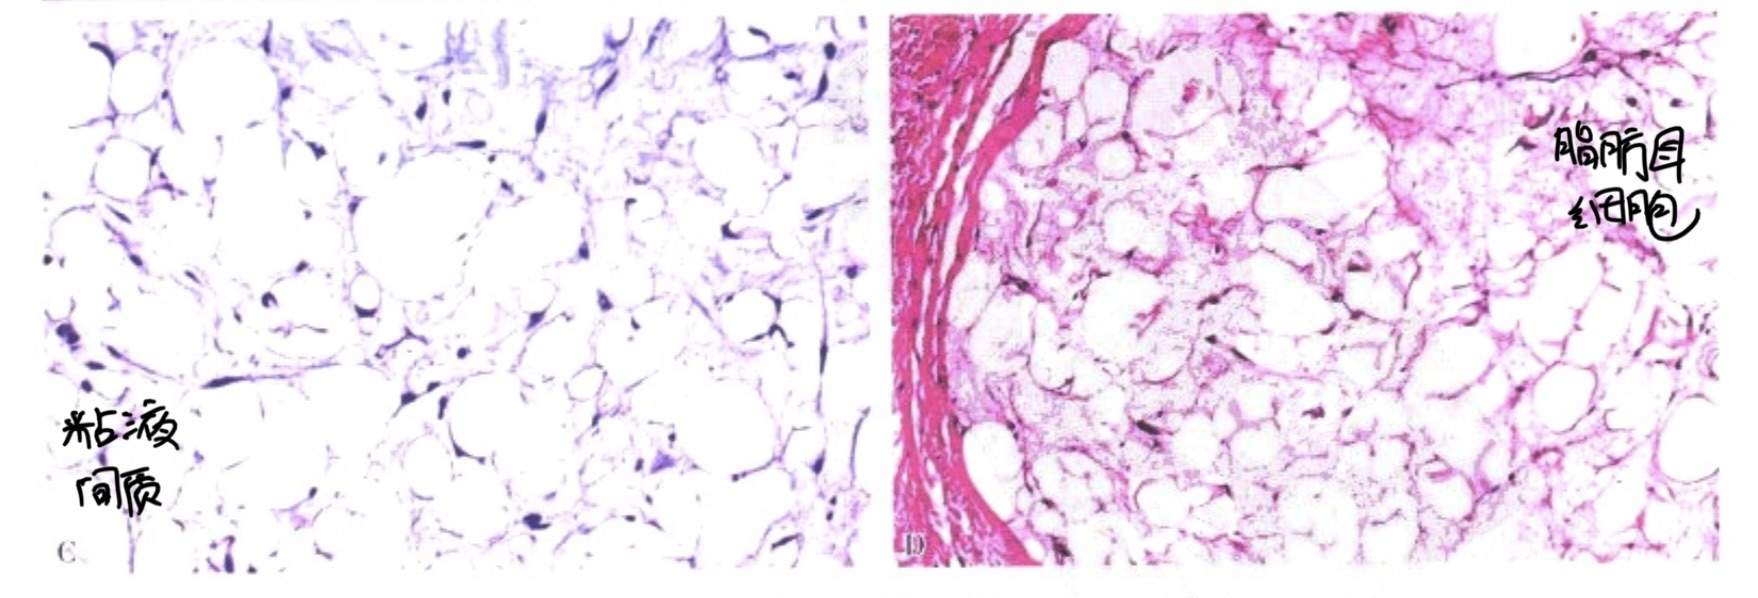

3、良性成脂肪细胞脂肪瘤(良性脂肪母细胞瘤)

选它是因为它会考!

要点:儿童、头颈部、不同分化程度的脂肪细胞无异型无病理性核分裂象。如图:

4、髓性脂肪瘤

也是因为会考!

考点:好发于肾上腺,考试逻辑:发生于深部脂肪组织的良性肿瘤(一般深层脂肪组织往往是肉瘤)。如图: